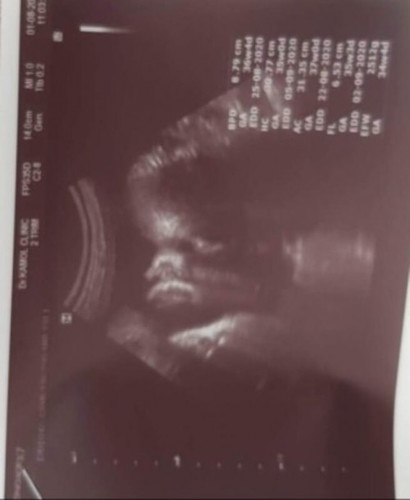

33w+4 dตอนนี้น้ำหนัก 2512 g.

วันนี้ออสตินมีนัดกับลุงหมอครับลุงหมอนัดผ่าคลอดวันที่5ก.ย. แต่ถ้าแม่ปวดท้องก่อนกำหนดคุณแม่ต้องคลอดเองหนูต้องรอให้ถึงวันที่5นะครับ Austinหนุ่มน้อย🇹🇭💕🇦🇺